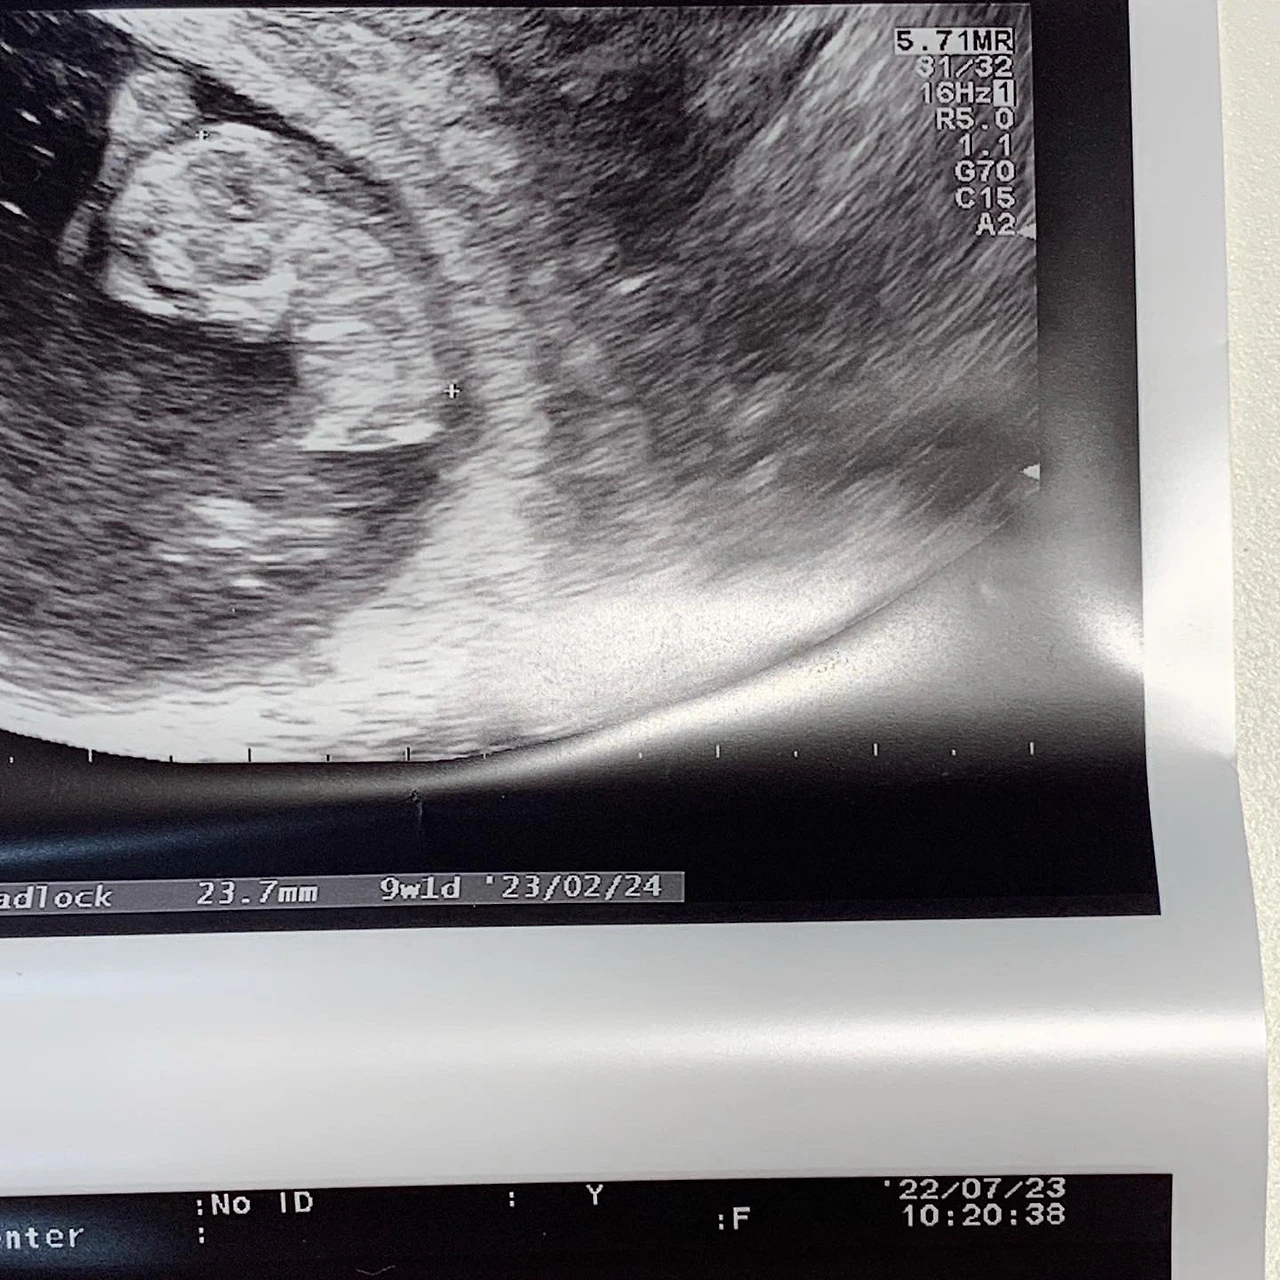

9주차 초음파 사진

아메바 같던 덩어리가 2등신으로 변했다. 이제 2cm를 갓 넘기면서 지난주보다 조금 더 또렷하게 팔과 다리, 머리와 턱이 분리되어 보였다. 정면으로 젤리 곰 같은 모습은 못 봤지만 덩어리에 비해 조금 더 진화된 모습.

- 아기 크기 2.3cm